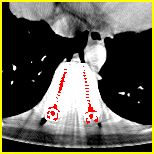

Effect of metal mask projection (SE0-Net vs SE-Net). From Table 1, we can observe the use of instead of improves the performance for at least 4.1 dB in PNSR and reduces MSE from 0.95219 to 0.00074 for all metal sizes. The groups with large metal implants benefit more than groups with small metal implants. As shown in Fig. 4, the artifacts in metal trace of SE0-Net are over-removed or under-removed, which introduces bright and dark bands in the reconstructed CT image. With the help of , SE-Net can suppress the artifacts even when the metallic implants are large and the surrogate data are more consistent with the correct data outside the metal trace.

Effect of sinogram padding (SE-Net vs SEp-Net). Sinogram padding mainly improves the performance in the group with the largest metal objects, with a PSNR gain of 0.15 dB and an MSE reduction of 0.00048. As shown in Fig. 4, the model with sinogram padding restores finer details of soft tissue between large metallic objects because more correct information is retained by periodic padding than zero-padding.

Effect of learning with (SEp-IE-Net vs Ours). When is jointly restored with the corrupted , the sinogram correction performance is affected with an increment of 0.00033 in MSE and of 0.7 dB in PSNR. More details of soft tissue around metal are retained and the image becomes sharper, as shown in Fig. 4.